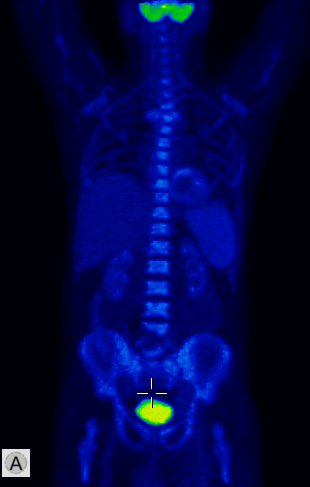

Among the general characteristics of isotope examinations, besides the ability to gain functional information, it is important to mention that – derived from the tracer principle – the examinations are highly sensitive, so the pathological processes can be detected at an early stage. SPECT is able to detect nano-molar radiotracer concentrations, while PET picks up signals coming from pico-molar radiopharmaceutical quantities. The higher sensitivity is due to the fact that functional alterations of metabolism usually precede detectable morphological changes of the tissues, thus functional studies allow earlier and more precise diagnostics. Another aspect of higher sensitivity is that in an optimal scenario, the biologic contrast between normal and pathologic function is very high. Therefore, signal intensity of a normal tissue process will be much lower than that of a pathologic one, making them easily distinguishable on the image. (Figure 2.)

Test iframe

2. FDG PET Maximum Intensity Projection (MIP) image. There is a large biological contrast between the normal and the pathologic tissues. Right sided breast cancer, ipsilateral metastatic lymph nodes and multiplex metastases in the lung. Physiologically elevated FDG uptake is seen in the brain, salivary glands, tonsils, liver and the spleen as well as in the bone marrow and at certain segments of the intestines. Also, there is increased FDG activity in the kidneys and the urinary bladder due to excretion.